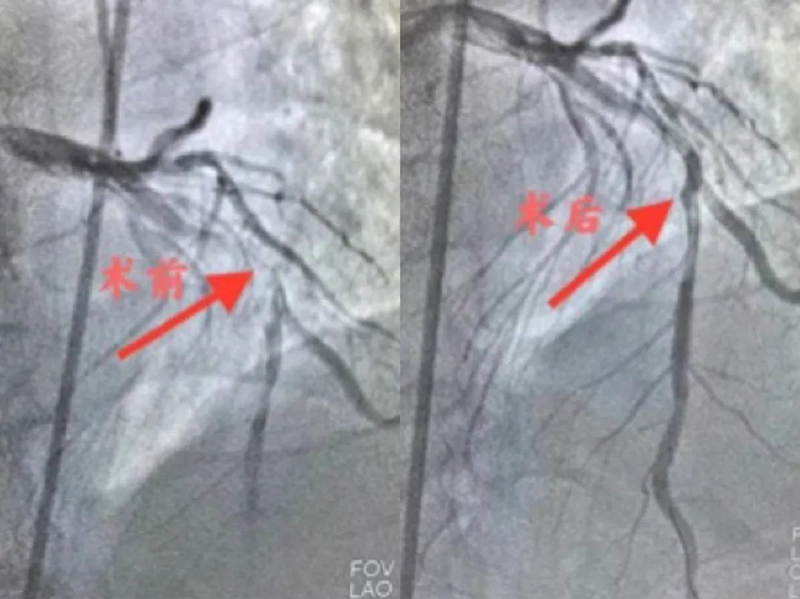

在心血管内二科于红波主任的指导下,在场医护争分夺秒开始抢救,胸外按压、电除颤等,大家迅速、沉稳、有序的密切配合着。经过20分钟高效救治,患者终于恢复窦性心律,生命体征逐渐平稳,送至介入中心继续治疗。医生为患者行冠脉造影显示前降支中段可见99%偏心狭窄,D1口部60%狭窄,回旋支中段可见99%狭窄,右冠状动脉中段可见70%偏心狭窄,远段可见50%偏心狭窄,于前降支植入支架1枚。